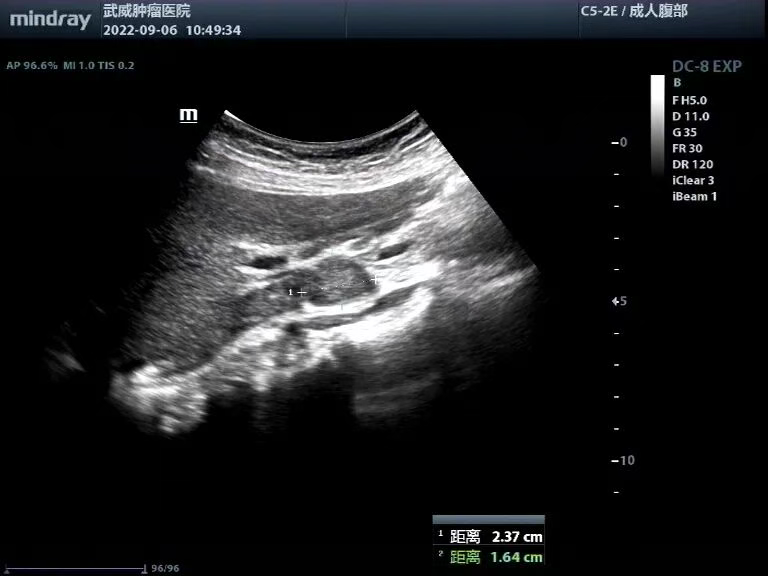

【常规超声显像】肝脏回声均匀,未见明显占位性病变;胆囊大小形态正常,囊壁增厚毛糙,胆囊腔内底部见大小30x24mm低回声团块,边界欠清,内部回声欠均匀,见点状强回声,其内见条状血流信号;肝内外胆管未见扩张,显示段内未见明显异常回声(图1)。

图1 胆囊腔底部低回声团块,内见条状血流信号